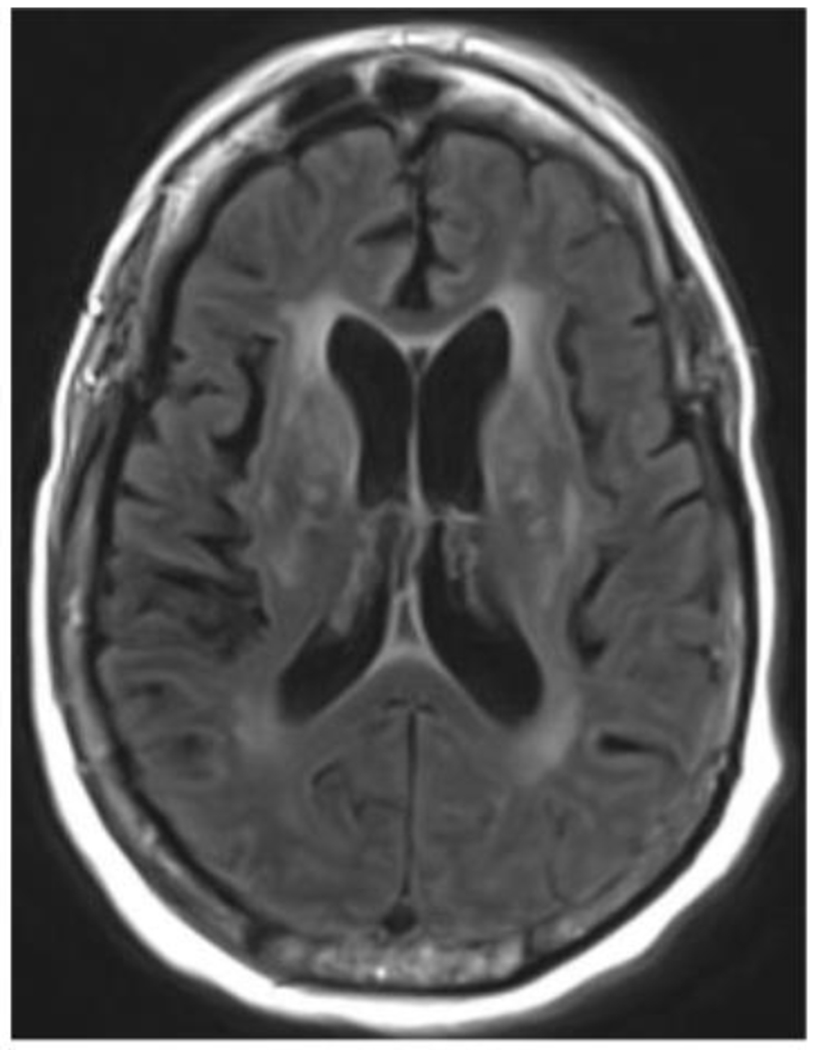

Cache Valley virus (CVV) is a mosquito-borne virus that is a rare cause of disease in humans. In the Fall of 2020, a patient developed encephalitis six weeks following kidney transplantation and receipt of multiple blood transfusions.

CVV was detected in CSF from the index patient by mNGS, and this result was confirmed by RT-PCR, viral culture, and additional whole genome sequencing. The organ donor and other organ recipients had no evidence of infection with CVV by molecular or serologic testing. Neutralizing antibodies against CVV were detected in serum from a donor of red blood cells received by the index patient immediately prior to transplant. CVV neutralizing antibodies were also detected in serum from a patient who received the co-component plasma from the same blood donation.

Our investigation demonstrates probable CVV transmission through blood transfusion. Clinicians should consider arboviral infections in unexplained meningoencephalitis after blood transfusion or organ transplantation. The use of mNGS testing might facilitate detection of rare, unexpected infections, particularly in immunocompromised patients.